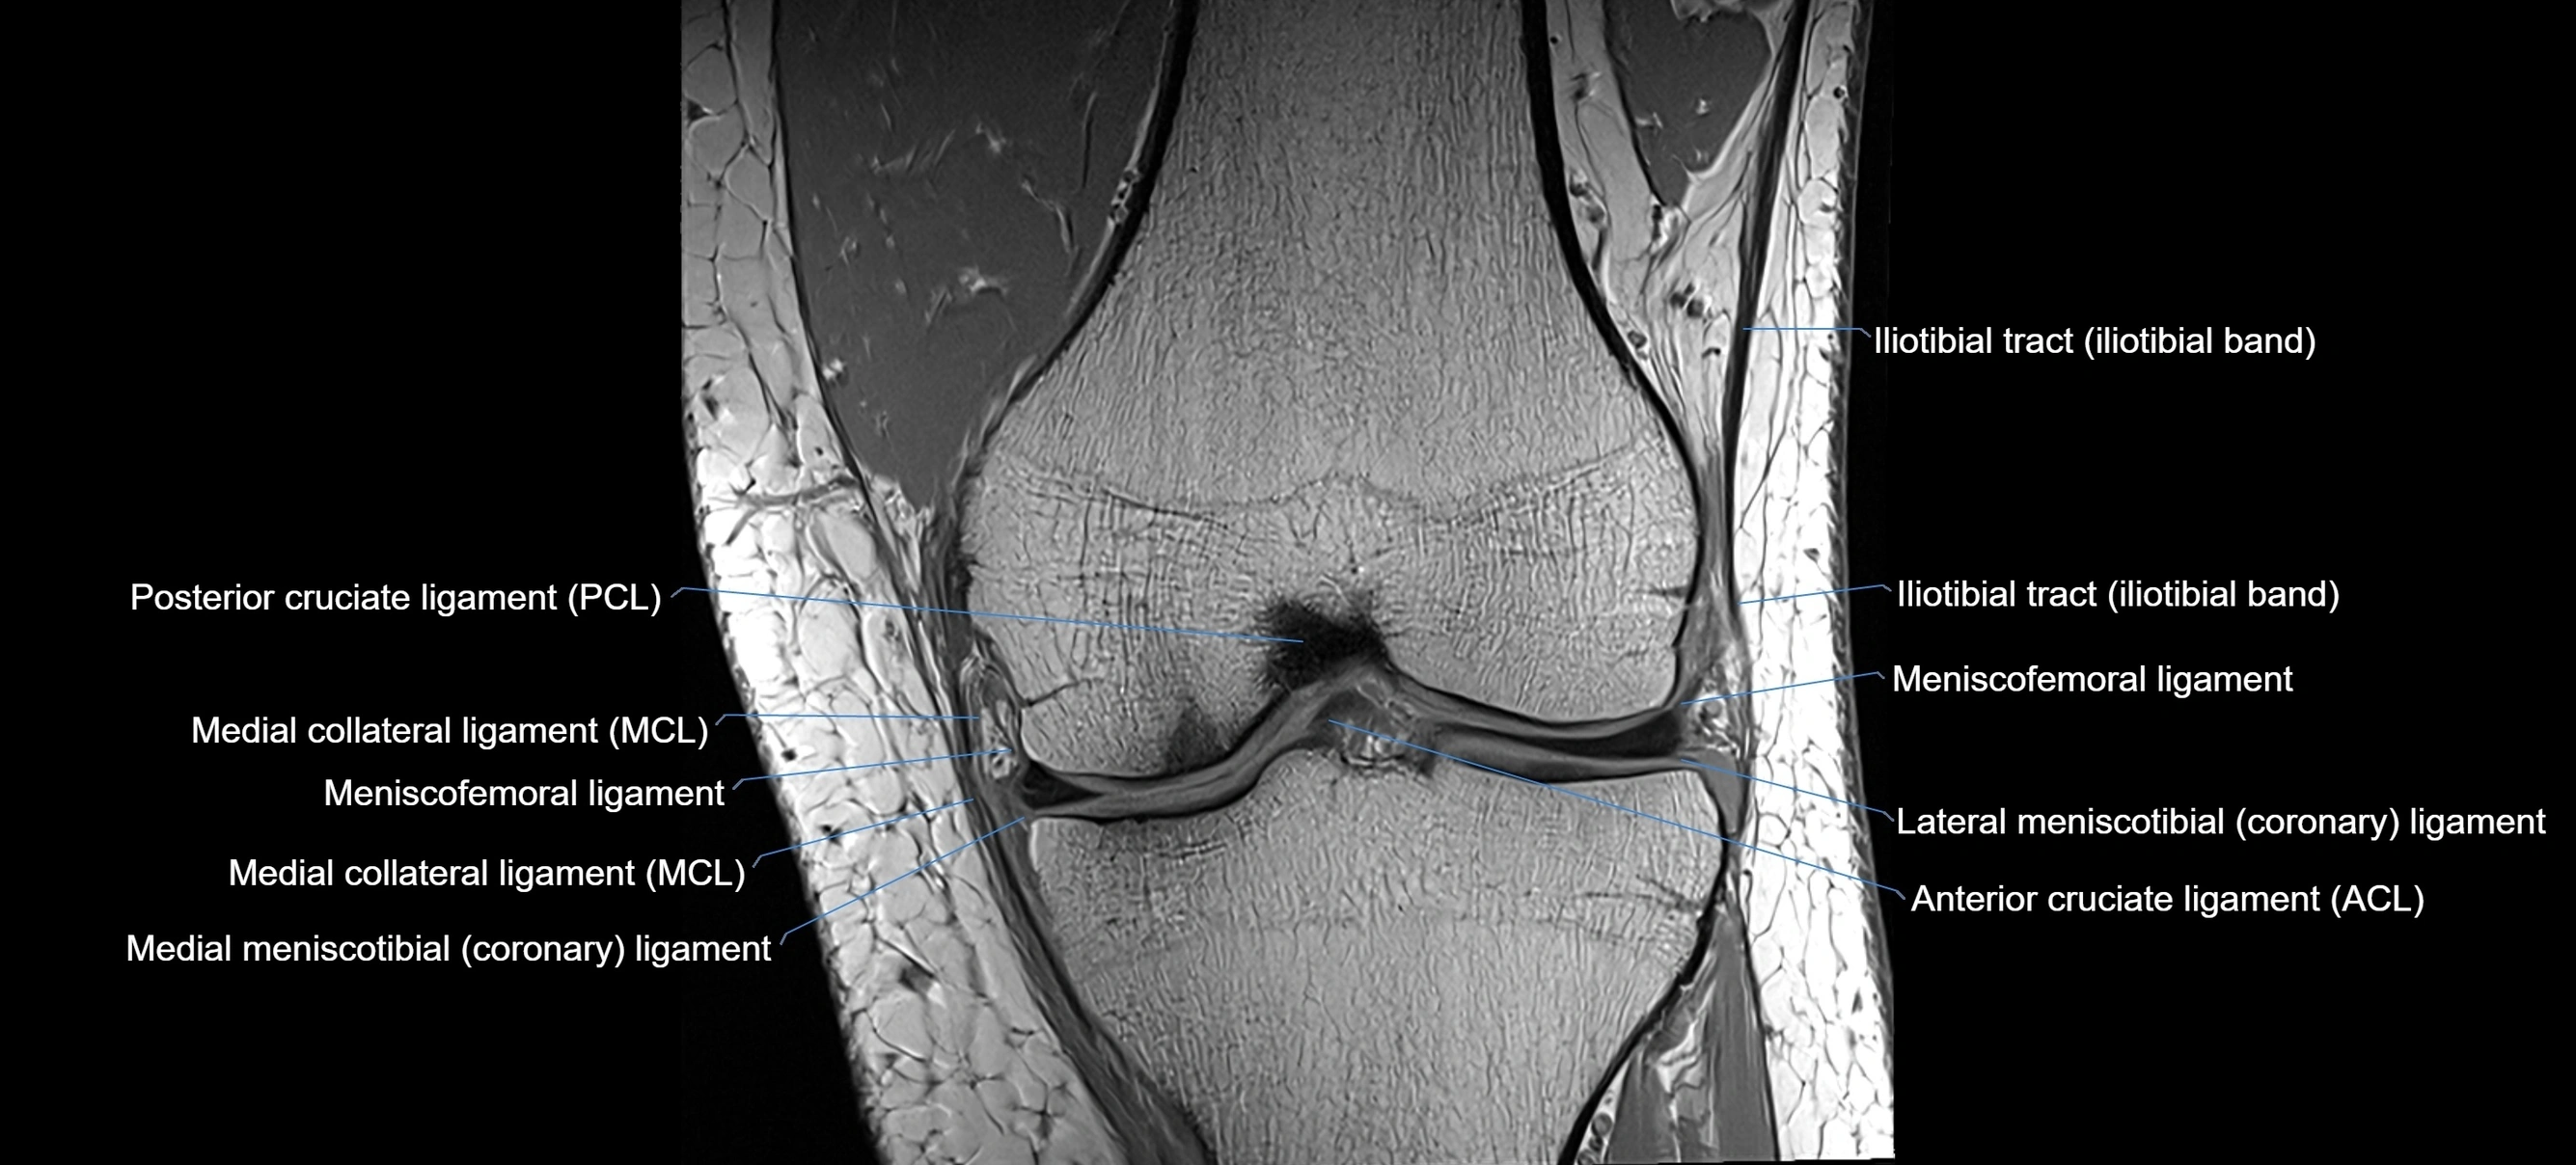

MRI Appearance

T1-weighted images:

• Normal ACL appears as a low-signal band-like structure crossing the intercondylar notch

• Surrounded by intermediate signal synovial fluid and fat planes

T2-weighted images:

• Normal ACL remains low signal

• Partial or complete tears appear as discontinuity, increased signal, or fiber laxity

MRI images

image